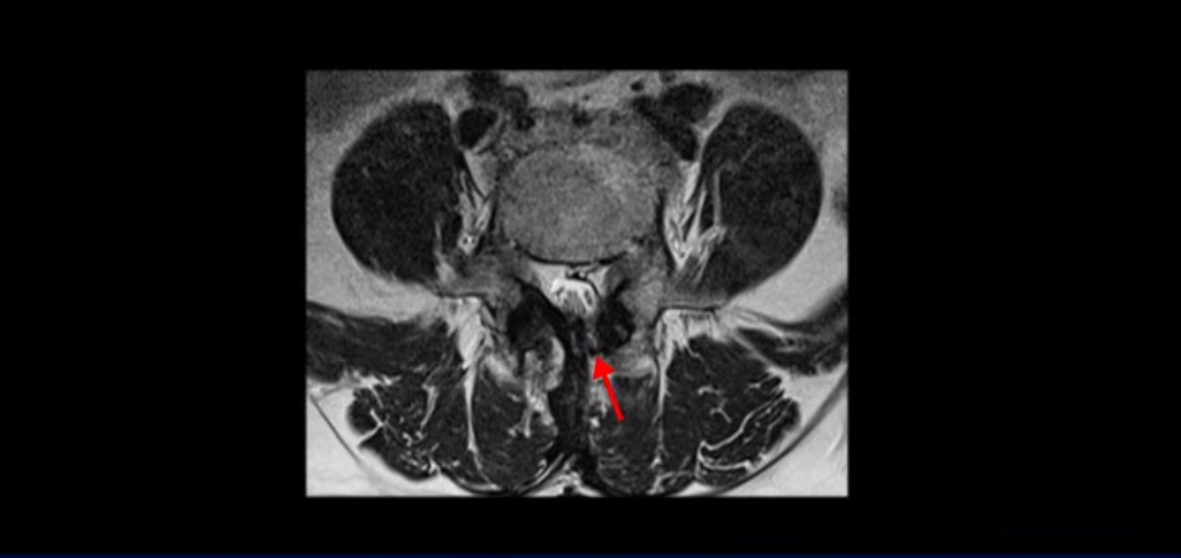

5번 1번도 왼쪽 후궁을 열고 수술 받았습니다.

하지만 중심성 협착은 여전히 심한 상태입니다.

이분은 오른쪽, 왼쪽 다리에 모두 방사통이 심하고 왼쪽 다리에 마비 증상, 즉 풋드랍(족하수) 증상이 있습니다. 왼쪽 신경 가지가 빠져나가는 추간공을 보면 두 마디가 좁아져 있습니다.

이런 신경 구멍이 좁아져 있는 걸 협착이라고 합니다.

이미 앞선 두 번의 수술로 뼈와 인대 등을 일부 제거해서 안정성이 떨어진 상태에서 추가로 수술하려니까 척추가 너무 불안정해져 무너질 게 걱정되니까 이번에는 나사 박는 유합술을 권유 받은 겁니다. 이런 환자분들의 방사통과 마비 증상이 어떻게 수술 없이 좋아질 수 있을까요? 치료는 어떻게 하는 걸까요?